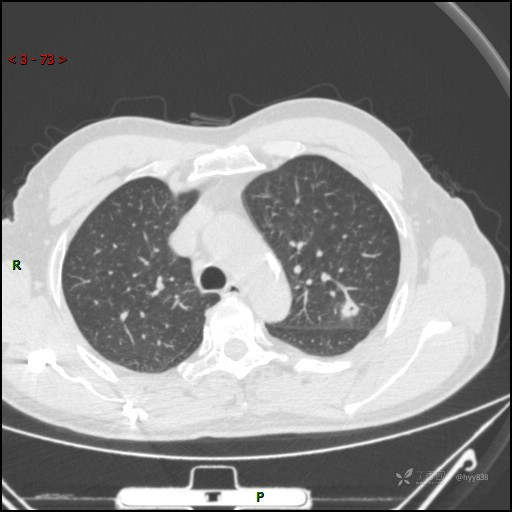

又遇恼人的肺结节,囊腔 VS 空洞 VS 空泡,欢迎讨论---结果公布~

主诉:发现左肺结节半月

简要病史:患者半月前因双眼翼状胬肉于我院眼科就诊行手术治疗,完善胸部CT发现左肺结节,未行特殊处理,偶有刺激性干咳,每于受凉后及饮冷水后发作,休息后可自行缓解,无发热、恶心呕吐、胸痛咯血,现为求进一步诊治,于我院就诊,门诊以“左肺结节”收入我科。 起病以来,患者食欲尚可,大小便正常,睡眠、精神可,体力、体重无明显变化。

临床诊断:肺结节

胸部CT平扫